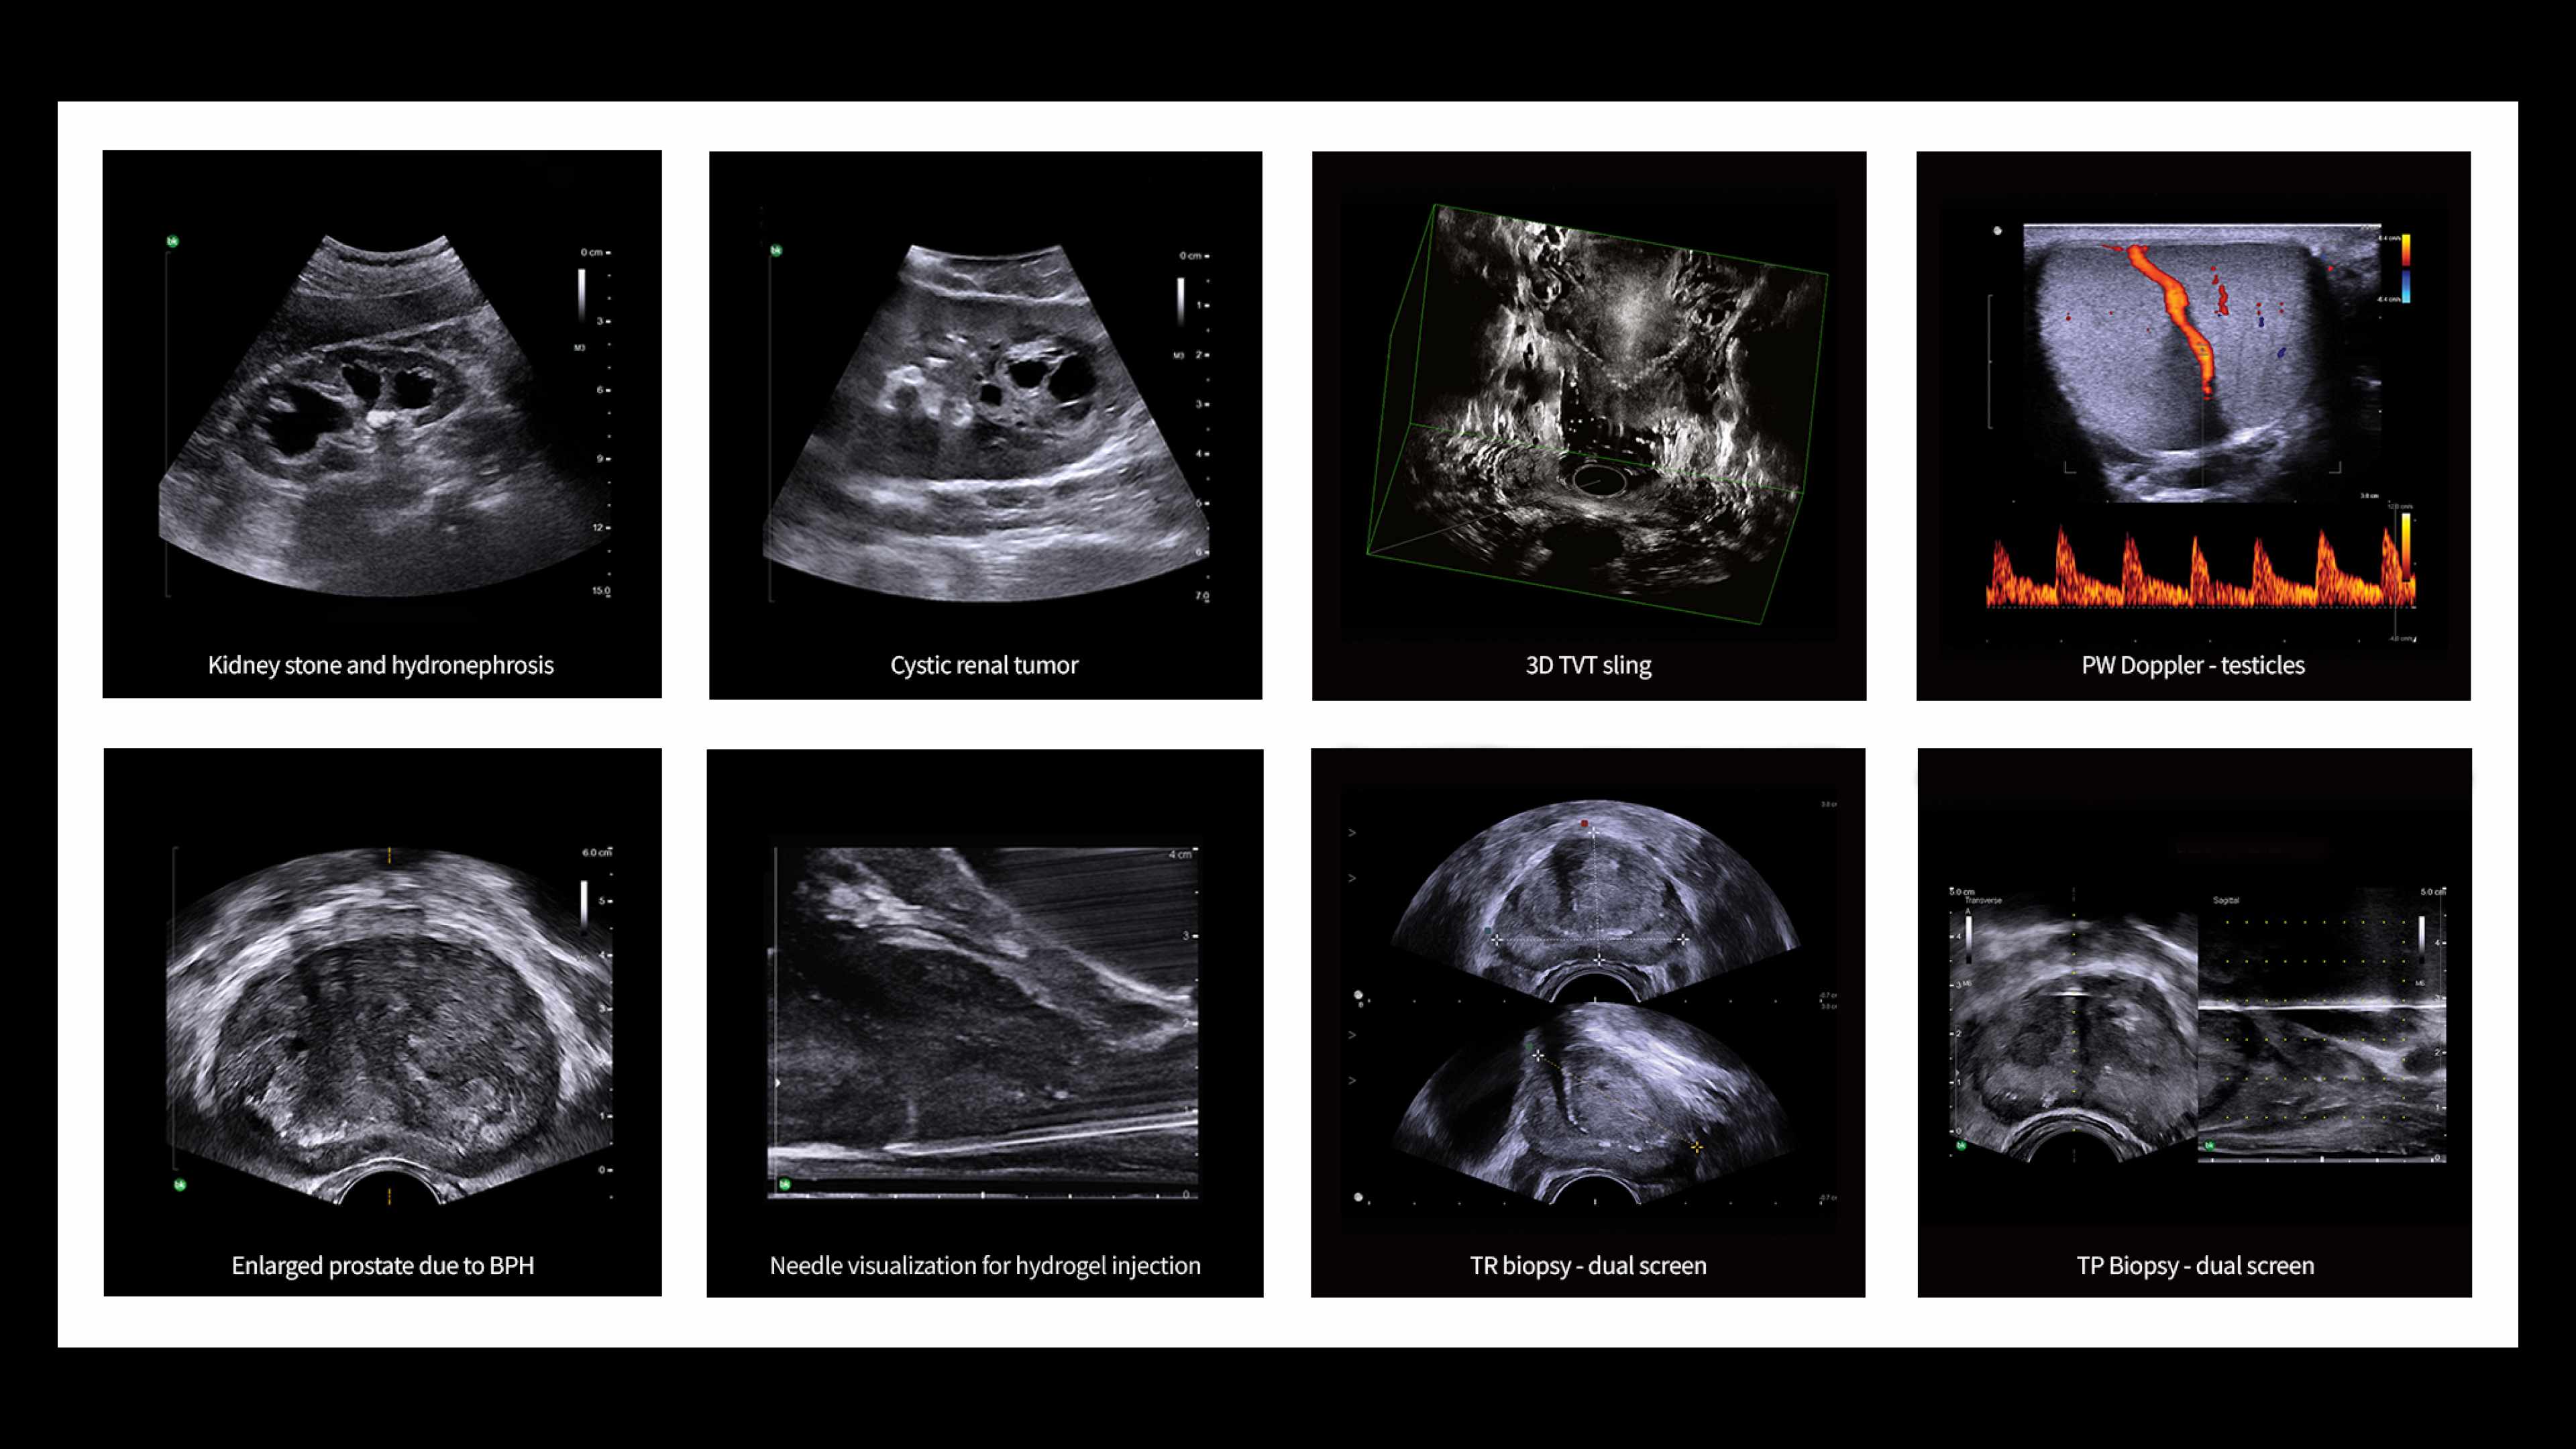

Avalie rapidamente rins e a bexiga com o Diagrama Renal

Simplifique a documentação e forneça acompanhamento fácil para pacientes com suspeita de hidronefrose. Não há necessidade de digitar os achados; simplesmente atribua um rótulo a partir de uma lista previamente preenchida que se correlaciona com imagens.